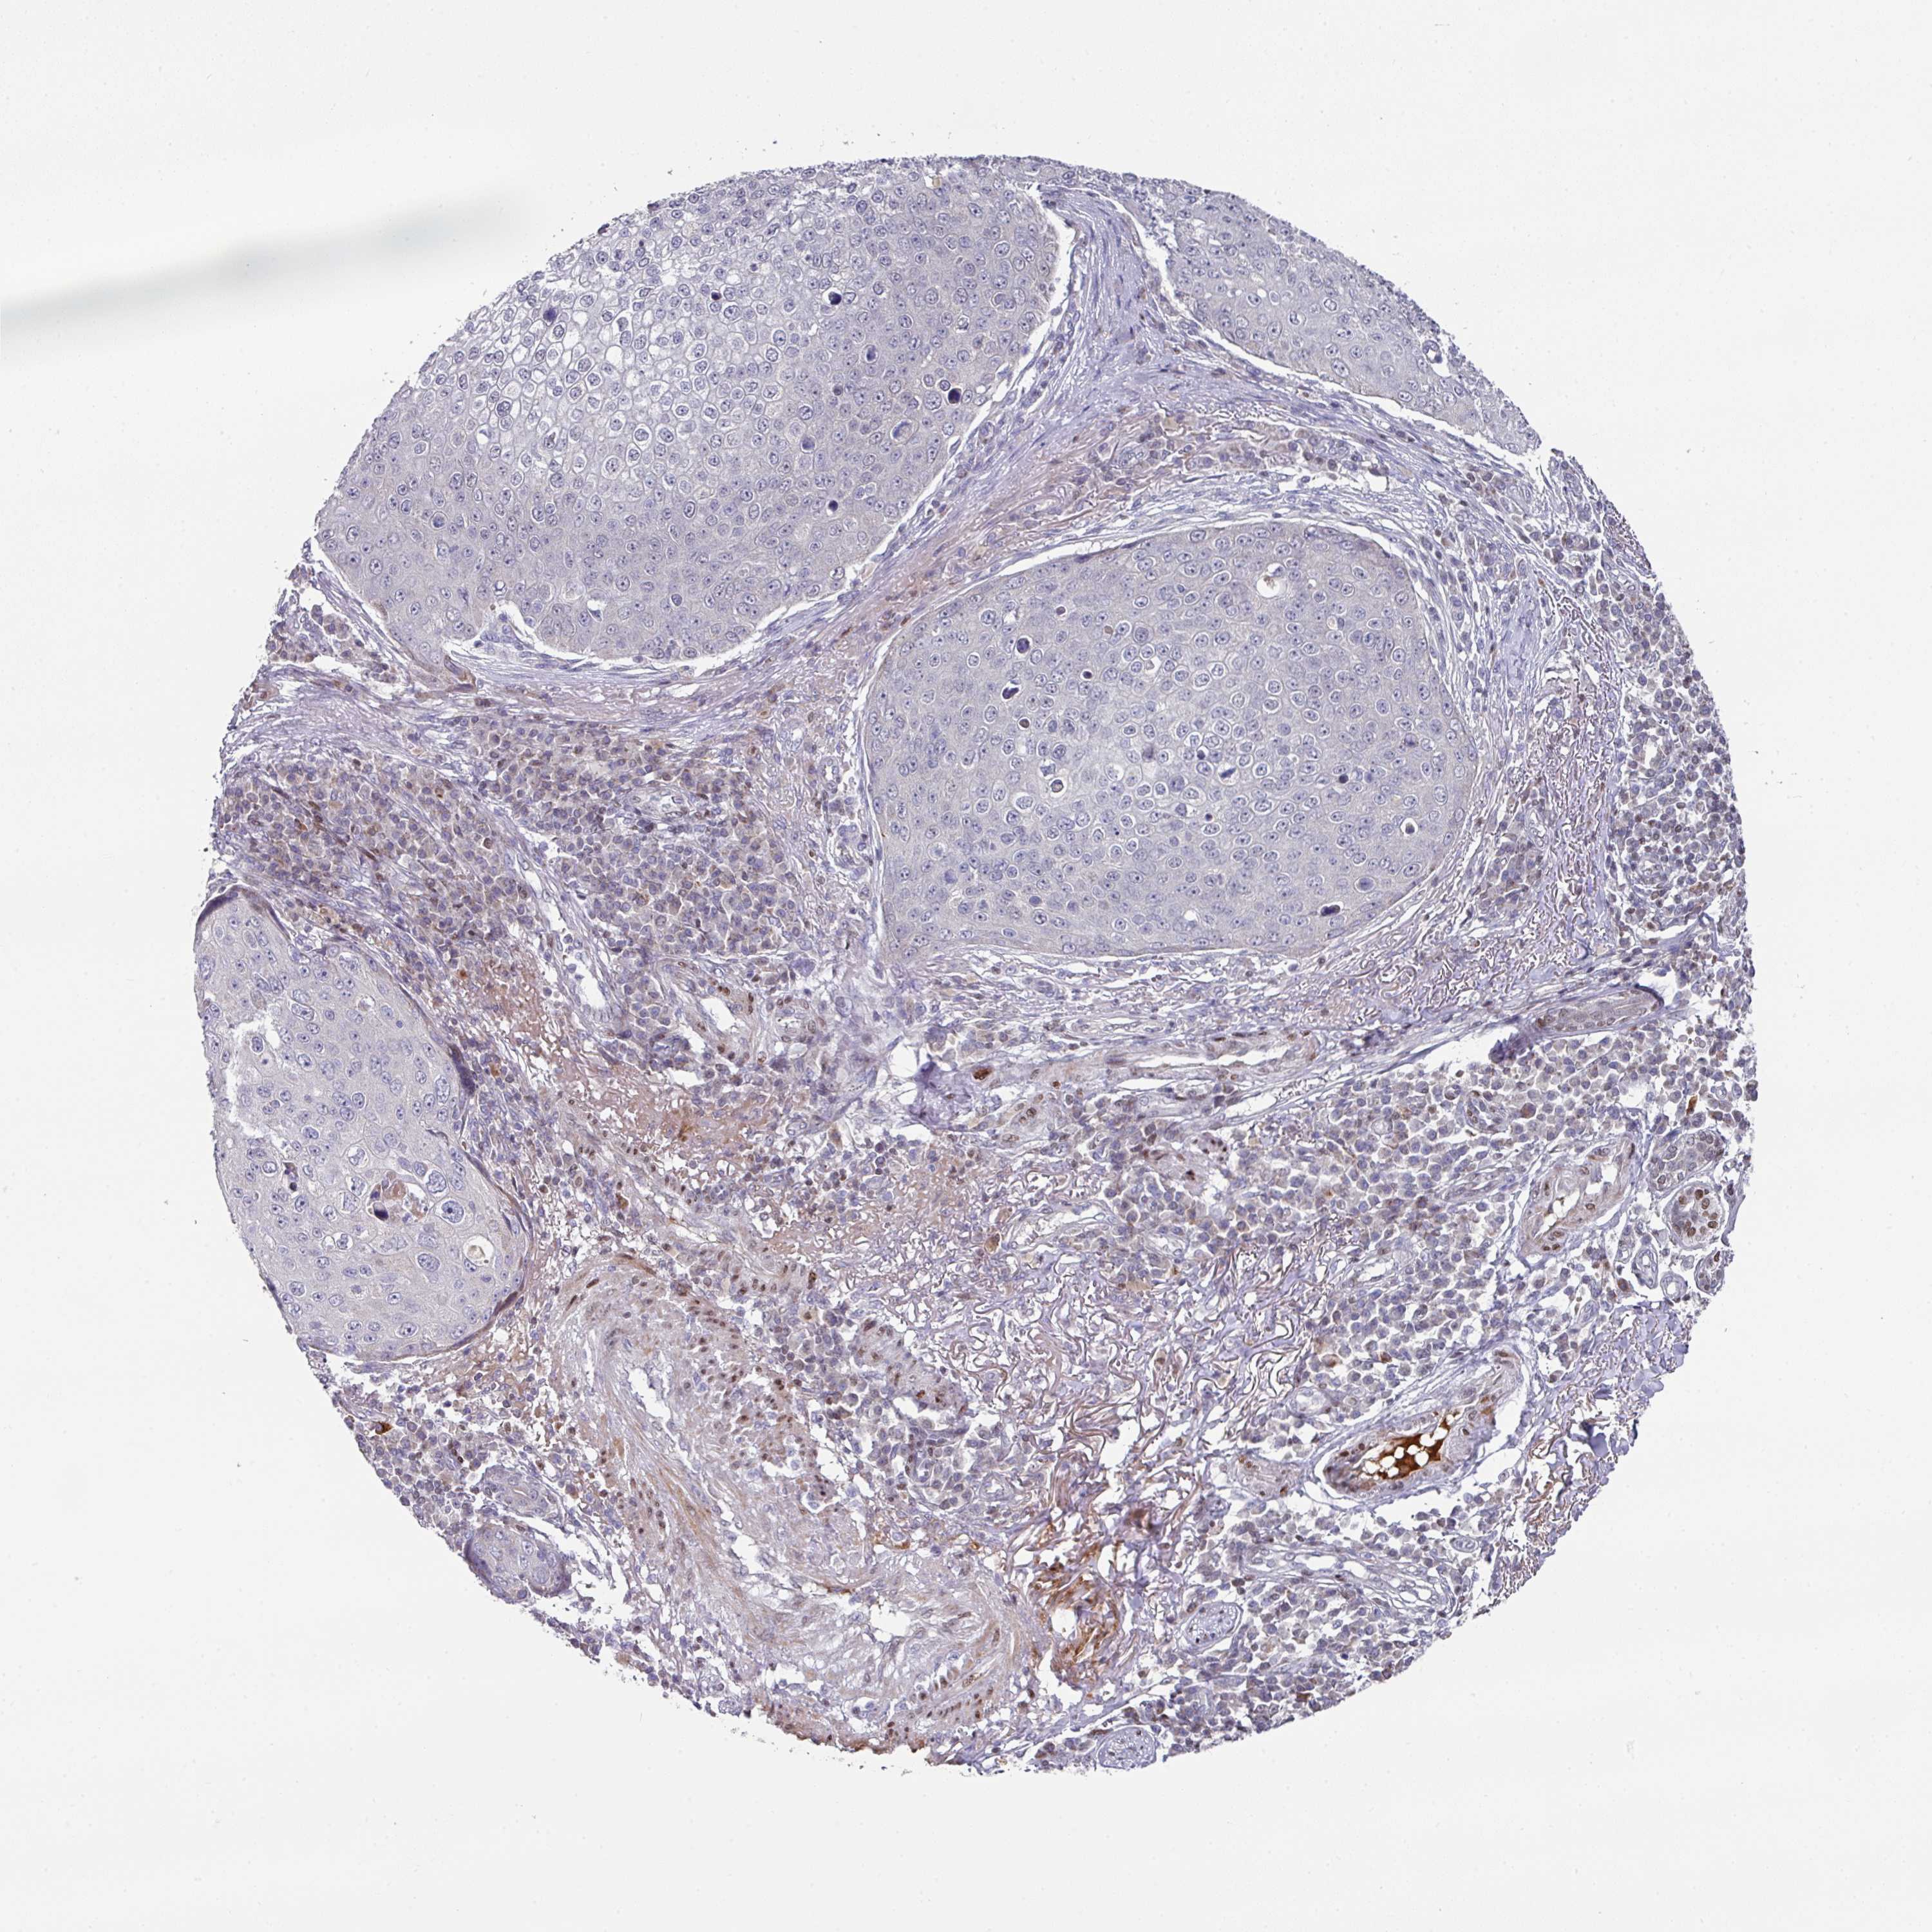

SKIN CANCER - Protein expressioni

A mouse-over function shows sample information and annotation data. Click on an image to view it in a full screen mode. Samples can be filtered based on level of antibody staining by selecting one or several of the following categories: high, medium, low and not detected. The assay and annotation is described here.

Each image is clickable and will lead to virtual microscopy that enables deeper exploration of all samples and also displays staining intensity scores, fraction scores and subcellular localization as well as patient and tissue information for each sample.

Antibody CAB011574

Squamous cell carcinoma, metastatic, NOS